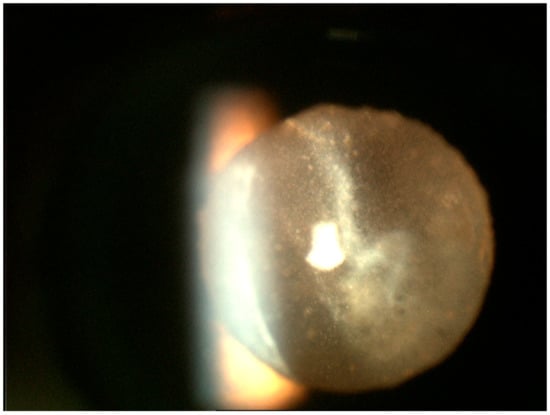

3. Clinical Features

Differential Diagnosis